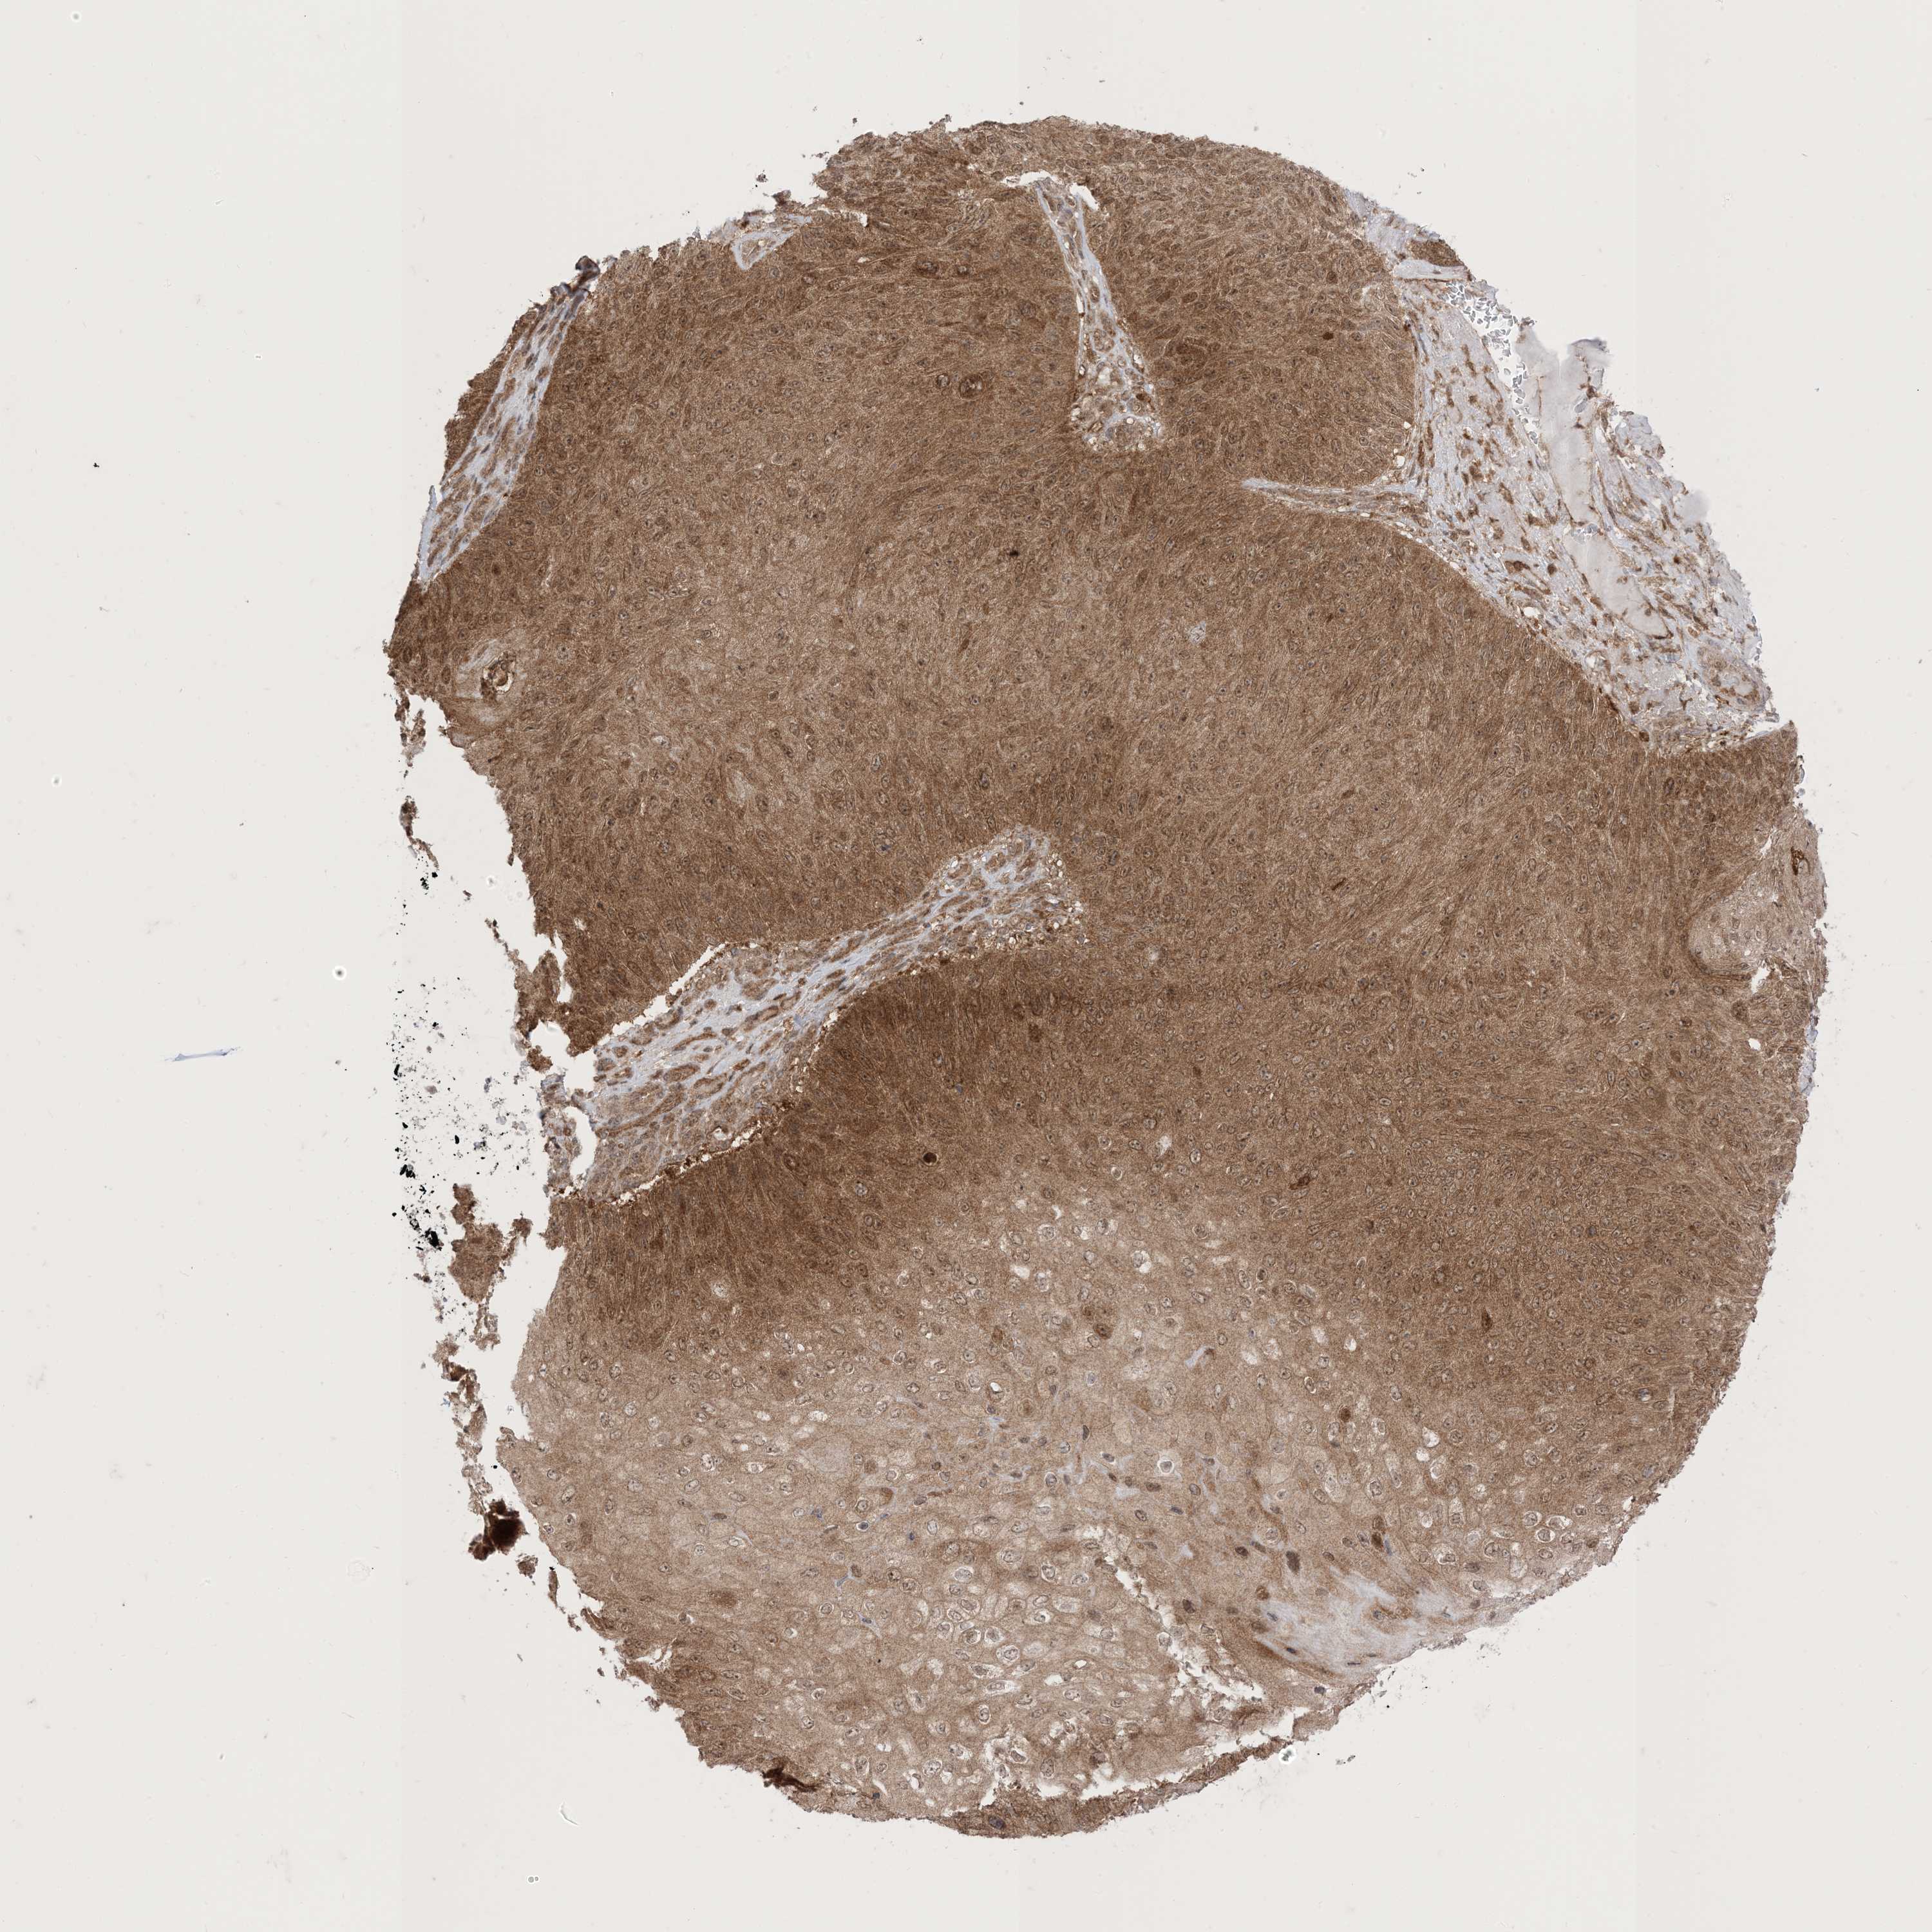

SKIN CANCER - Protein expressioni

A mouse-over function shows sample information and annotation data. Click on an image to view it in a full screen mode. Samples can be filtered based on level of antibody staining by selecting one or several of the following categories: high, medium, low and not detected. The assay and annotation is described here.

Antibody stainingi

Antibody staining in the annotated cell types in the current human tissue is reported as not detected, low, medium, or high, based on conventional immunohistochemistry profiling in selected tissues. This score is based on the combination of the staining intensity and fraction of stained cells.

Each image is clickable and will lead to virtual microscopy that enables deeper exploration of all samples and also displays staining intensity scores, fraction scores and subcellular localization as well as patient and tissue information for each sample.

CAB080052

Squamous cell carcinoma, metastatic, NOS